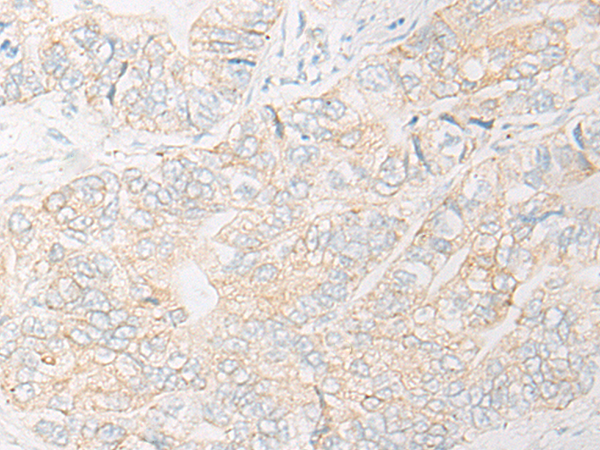

The image is immunohistochemistry of paraffin-embedded Human gastric cancer tissue using 47233(UQCR10 Antibody) at dilution 1/30. (Original magnification: ?00)

,

The image is immunohistochemistry of paraffin-embedded Human liver cancer tissue using 47233(UQCR10 Antibody) at dilution 1/30. (Original magnification: ?00)